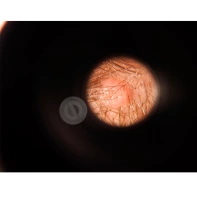

Процедура дерматоскопии

Как проводится дерматоскопия и что видит доктор при осмотре пациента.